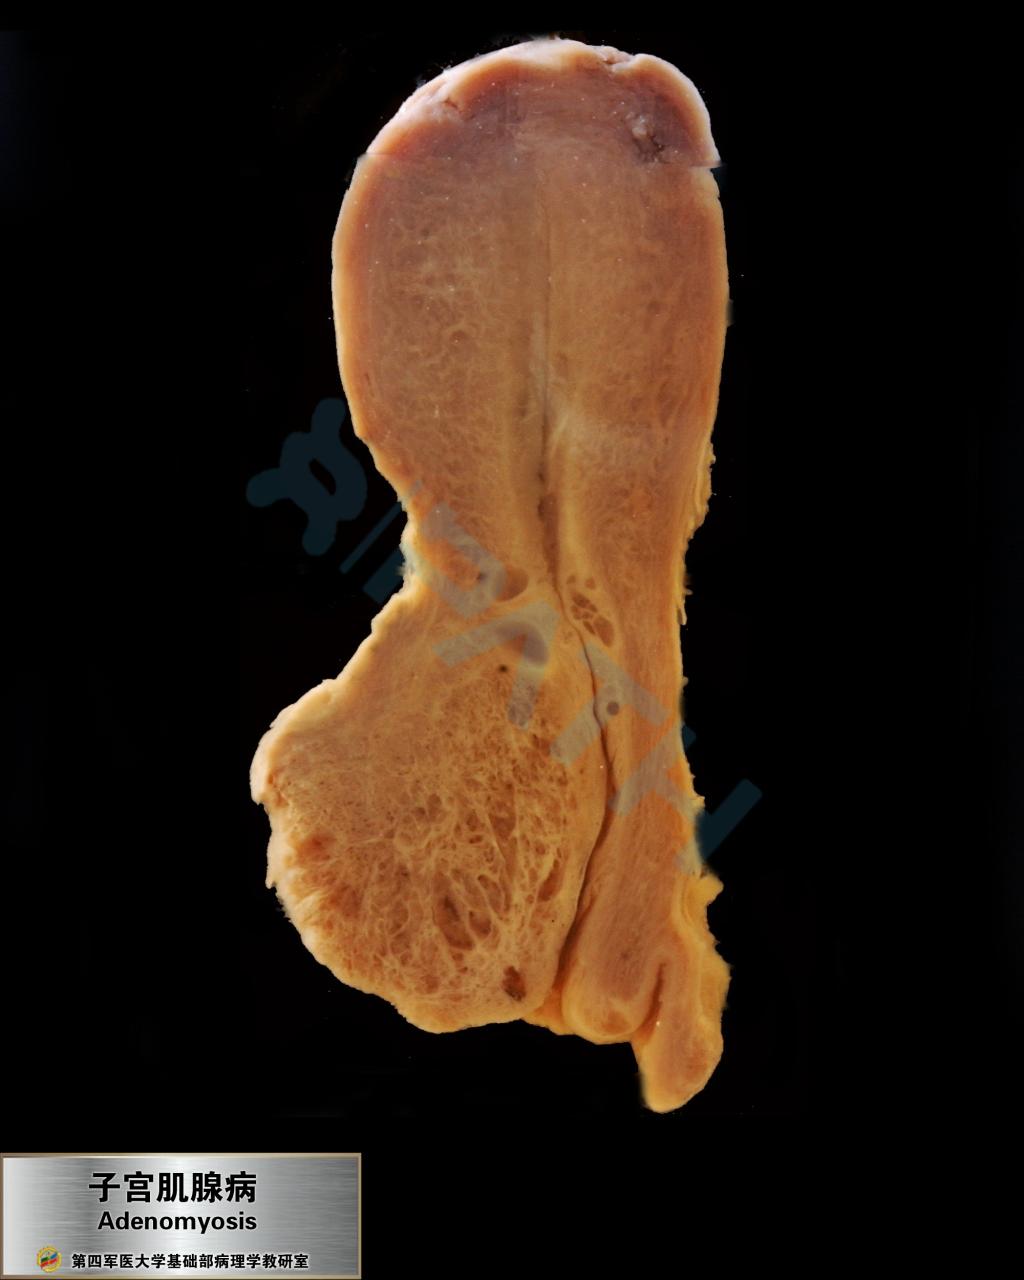

子宫腺肌病